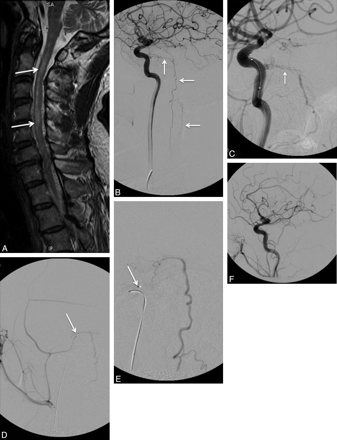

Spinal cord AVMs are evenly distributed along the spinal cord axis and may be located within the parenchyma (intramedullary) (Fig 1), the surface of the spinal cord (pial) (Fig 2), the epidural space (epidural) (Fig 3), or they may have a more complex anatomy with both intramedullary and extramedullary components without respect to tissue boundaries. The conus medullaris AVM13 represents a distinct type located on the conus medullaris or cauda equina and can extend along the filum terminale.

A, A 31-year-old patient presenting with quadriparesis secondary to intramedullary hemorrhage seen as hyperintensity in a sagittal T1-weighted MR image (arrow). B−D, The spinal angiograms show an intramedullary AVM (arrow) with arterial feeders from the ASA (arrowheads), which, at this level, is supplied by the right vertebral artery (C and D) and the left ascending cervical artery from the thyrocervical trunk (B). E, The AVM is embolized with n-BCA (arrow) with a microcatheter positioned via the left ascending cervical artery into the ASA branch feeding the nidus. Postembolization angiogram shows no residual supply to the nidus from the left ascending cervical artery, while the supply to the ASA is preserved (arrowhead). F, Postembolization right vertebral artery angiogram shows residual nidus (<30% of the total AVM nidus) and preserved flow into the ASA (arrowhead).